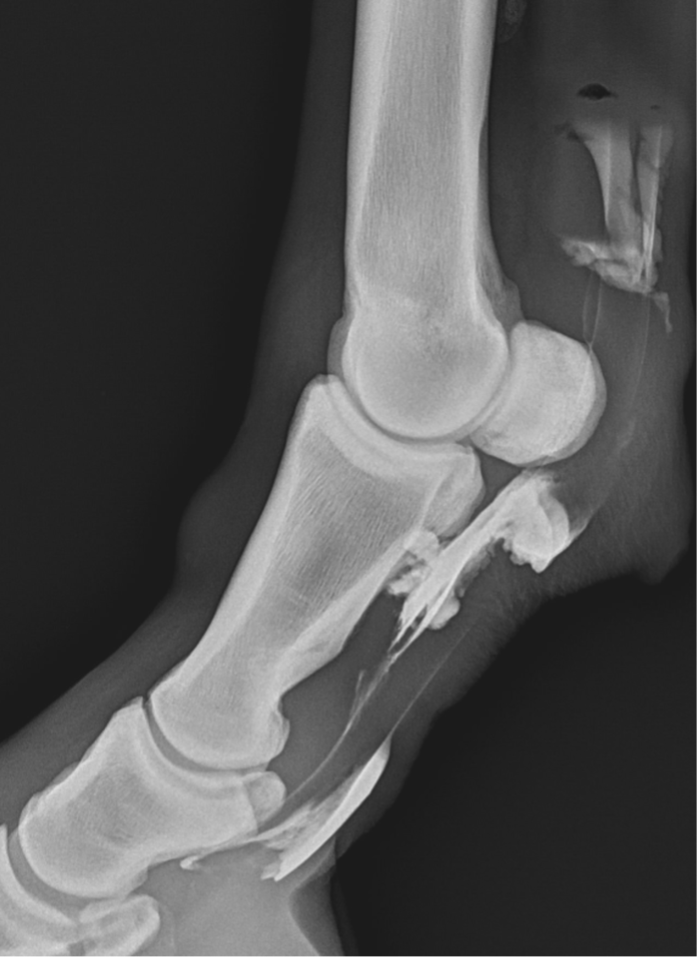

- The sheath is distended by anechoeic fluid. Arrow showing the swollen vincula and the arrowheads show swollen synovium surrounding the tendons.